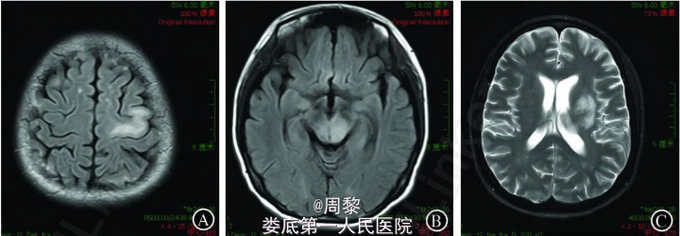

入院体检 :体温37 ℃,心率70次/min,呼吸16次/min,血压96/62 mmHg。双肺呼吸音清,未闻及干湿性啰音。心律规整,各瓣膜听诊区未闻及病理性杂音。神经系统检查 :意识清楚,言语清晰,双侧瞳孔等大等圆,直径约 3 mm,对光反应灵敏。额纹对称,右侧鼻唇沟变浅,伸舌居中。右上下肢肌力 4+ 级,左上下肢肌力 5 级,四肢肌张力正常。双侧 Babinski 征( -。脑膜刺激征阴性。CD4+ T 淋巴细胞检测结果 :CD4+62 个/μL,CD8+752 个/μL。HIV 病毒载量检测结果为83000拷贝/mL。血常规检查结果显示 :白细胞2.9× 10^9/L 、中性粒细胞2.1 × 10^9/L 、淋巴细胞0.6 ×10^9/L 、血小板180× 10^9/L 、红细胞 4.29×10^12 /L 、血红蛋白136g/L。CT 检查结果 :脑梗死。给予抗病毒、改善脑循环 、对症支持治疗,不见好转,病情加重,于 2013-01-08转入济宁医学院附属医院治疗。入院体检 :精神差,反应迟钝,言语迟缓。颈略抵抗。双侧瞳孔对光反应迟钝,右眼不能外展、上视 、下视,左眼内收 、外展受限,不能上视 、下视,无偏盲。右侧鼻唇沟变浅,伸舌右偏。右侧上肢肌力 0级,下肢3级,左手指鼻准稳。右偏身痛觉减退。双 Hoffmann征 、Babinski 征阴性,床旁吞水试验阴性。颅脑 MRI 平扫结果显示额叶 、顶叶、基底节、丘脑、左侧大脑脚 、延髓左侧见多发斑片状 、斑点状异常信号,呈长 T1 长 T2 异常信号,T2WI像 、FLAIR 像及 DWI 为高信号。小脑未见明显异常。MRA :未见明显异常。脑脊液检查 :无色透明,潘氏实验阳性,白细胞 4.0× 106 /L,蛋白720mg/L,葡萄糖4.5 mmol/L,氯化物 157 mmol/L,JC 病毒 DNA 阳性。

诊断:艾滋病(AIDS)伴发进行性多灶性脑白质病(PML)。治疗:给予抗病毒 、对症支持治疗,不见效果。